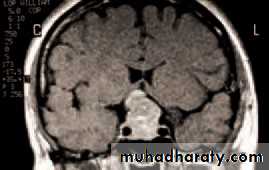

• RADIOLOGICAL IMAGING TECHNIQUES

• The CT and MRI scans have largely replaced skull and orbital X-rays in the imaging of the orbit and visual pathway. The newer diagnostic techniques have enhanced the diagnosis of orbital disease (e.g. optic nerve sheath meningioma) and visual pathway lesions such as pituitary tumours. They have also become the first line investigation in orbital trauma.

• A CT or MRI scan will help with the diagnosis. Again systemic investigation, for example to determine the site of a primary tumour, may be required.

• Fig. 4.5 A CT scan showing a left sided orbital secondary tumour.